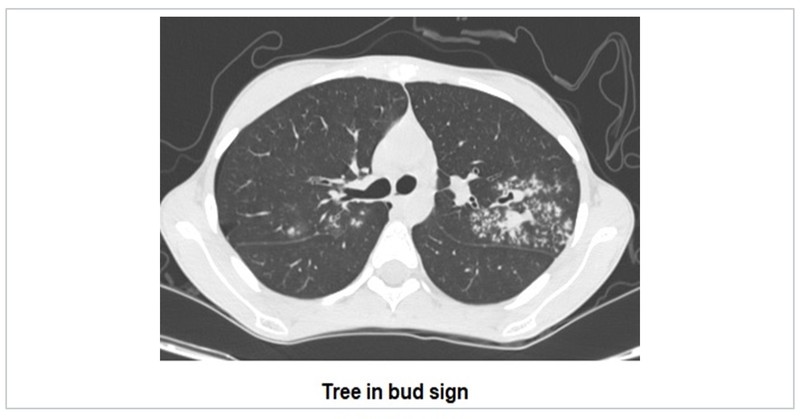

Tree in bud sign

Tree-in-bud sign suggests multiple areas of centrilobular nodules with a linear branching pattern. Initially described in patients with endobronchial tuberculosis, it is now recognised in a large number of conditions again ranging from infections, inflammations, vasculitis to malignancies.